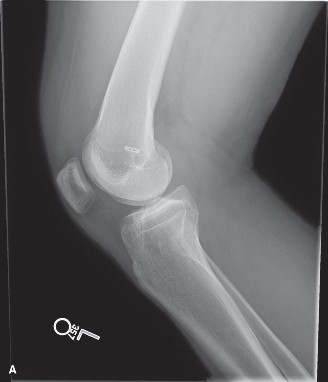

CASE 2 An 18-year-old soccer player injures her knee during competition. She r…